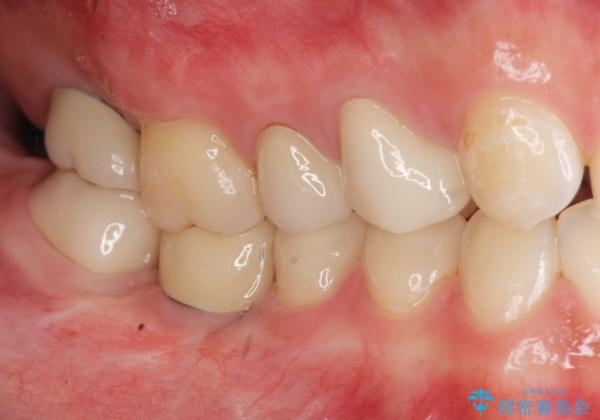

インプラントを用いた臼歯部欠損補綴

- 上下1本づつの歯を失い、噛めないことの改善を求めて来院されました。

保存可能な歯の虫歯・根管治療を行い、喪失した部分はインプラントを埋入、オールセラミックジルコニアクラウンを製作し審美的に仕上げていきます。

- 120万円(仮歯×6・ファイバーコア×2・ジルコニアクラウン×6・インプラント×2・チタンカスタムアバットメント×2)費用は治療当時の料金となります

今回下顎の欠損部位はブリッジも検討されましたが、並行性の観点から最後方臼歯の神経を取るリスクを抑えるためインプラント治療を選択しました。